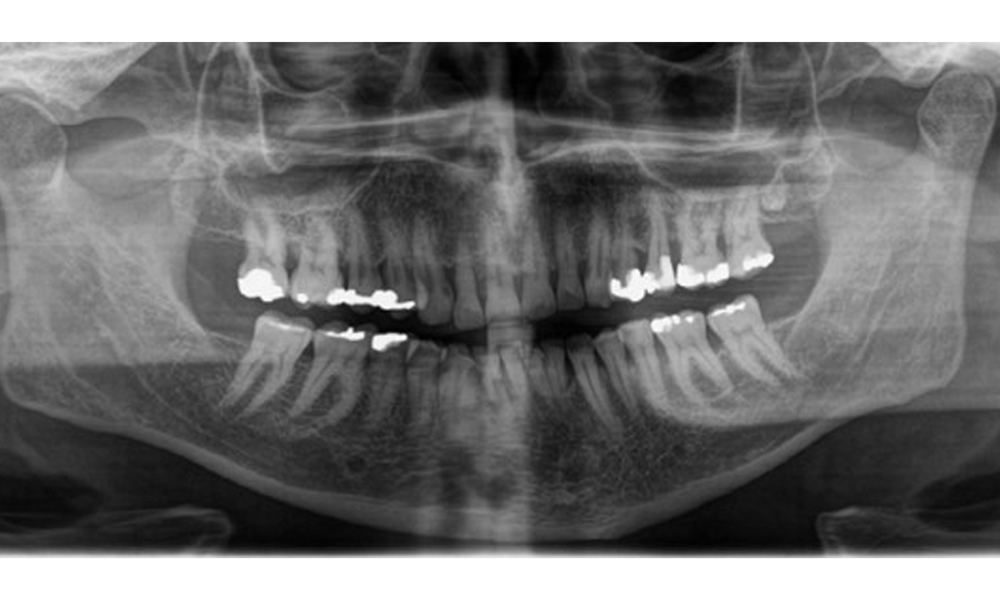

Radiological findings

There is fully dentulous adult dentition with generalized bone loss of between 20-50% and multiple areas of vertical bone loss. Radiological examination revealed no visible caries. (Fig. 7)